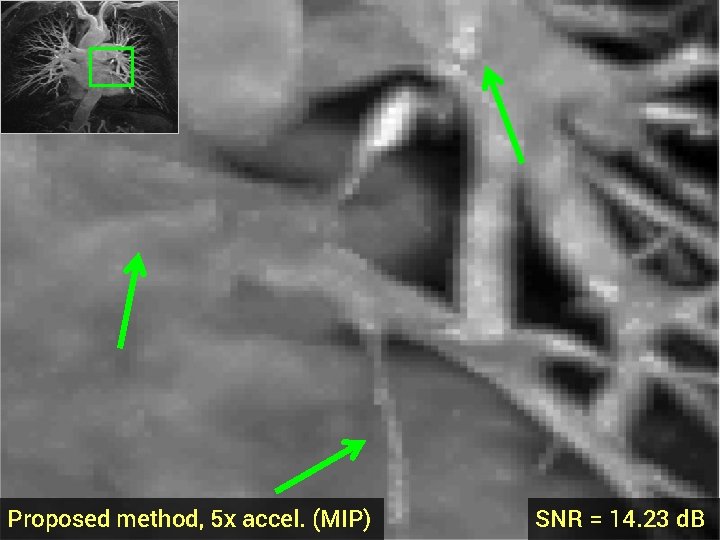

Total Variation (TV) penalty for CS-MRI § Promotes recons with sparse gradient <-> piecewise constant regions § Advantages: fast algorithms, easy to implement § Disadvantages: loss of detail at high accelerations § Ex: 3 -D MRA dataset, 5 -fold acceleration, random k-space samples Fully-sampled (MIP) TV recon, 5 x accel. , SNR = 13. 87 d. B

TV recon, 5 x accel. (MIP) SNR = 13. 87 d. B

Proposed method, 5 x accel. (MIP) SNR = 14. 23 d. B